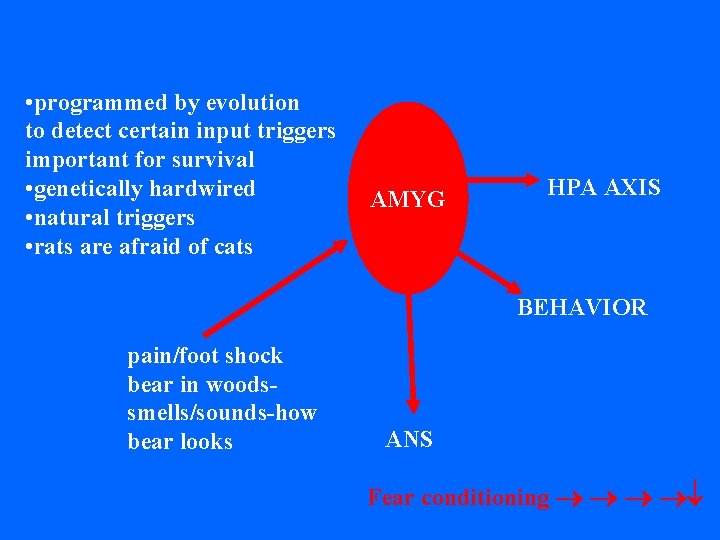

• programmed by evolution to detect certain input triggers important for survival • genetically hardwired • natural triggers • rats are afraid of cats AMYG HPA AXIS BEHAVIOR pain/foot shock bear in woodssmells/sounds-how bear looks ANS Fear conditioning